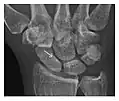

Occult osseous injuries may result from a direct blow to the bone by compressive forces of adjacent bones against one another or by traction forces during an avulsion injury. Lesions in the tibial plateau, hip, ankle, and wrist are often missed. In a tibial plateau fracture, any disruption of the posterior and anterior cortical rims of the plateau should be sought. Impaction of subchondral bone will appear as an increased sclerosis of the subchondral bone (Figure 1). In the hip, posterior acetabular fractures also present subtle radiographic findings. The acetabular lines should then be carefully examined keeping in mind that the posterior rim, which is harder to see on X-rays, is more frequently fractured than the anterior rim (Figure 2). In the wrist, detection of carpal bone fractures is often challenging, with up to 18% of scaphoid fractures radiographically occult. Carpal fractures, especially the scaphoid, are associated with the risk of avascular necrosis. In apparently normal wrist radiographs from symptomatic patients, if there is history of a fall on an outstretched hand with pain in the anatomic snuffbox, suggesting scaphoid injury, the initial examination with posteroanterior, lateral, and pronation oblique views must be complemented by other specific views such as supination oblique and the "scaphoid" view A careful examination of cortices for evidence of discontinuity or offset and cancellous bone for lucency is necessary (Figure 3).[1]

a

b

c

Figure 3: A 26-year-old man presenting with wrist pain after being assaulted. (a) Initial anteroposterior radiograph shows a subtle linear lucency within the scaphoid extending to the scaphocapitate articular surface that was overlooked (arrow). (b) Initial "scaphoid" view was negative. (c) Followup anteroposterior radiographs, 12 days later, shows obvious scaphoid fracture (arrows).[1]